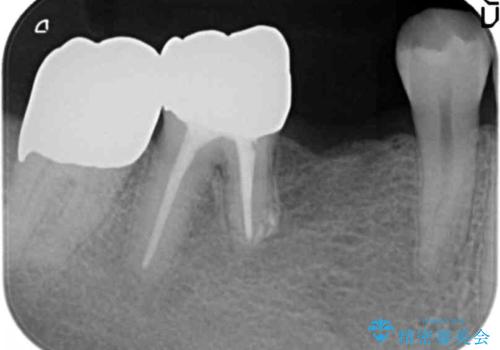

その後ブリッジの治療も希望され、オールセラミックのブリッジによる補綴を行いました。

右下⑥5④ブリッジ:オールセラミッククラウン スタンダード